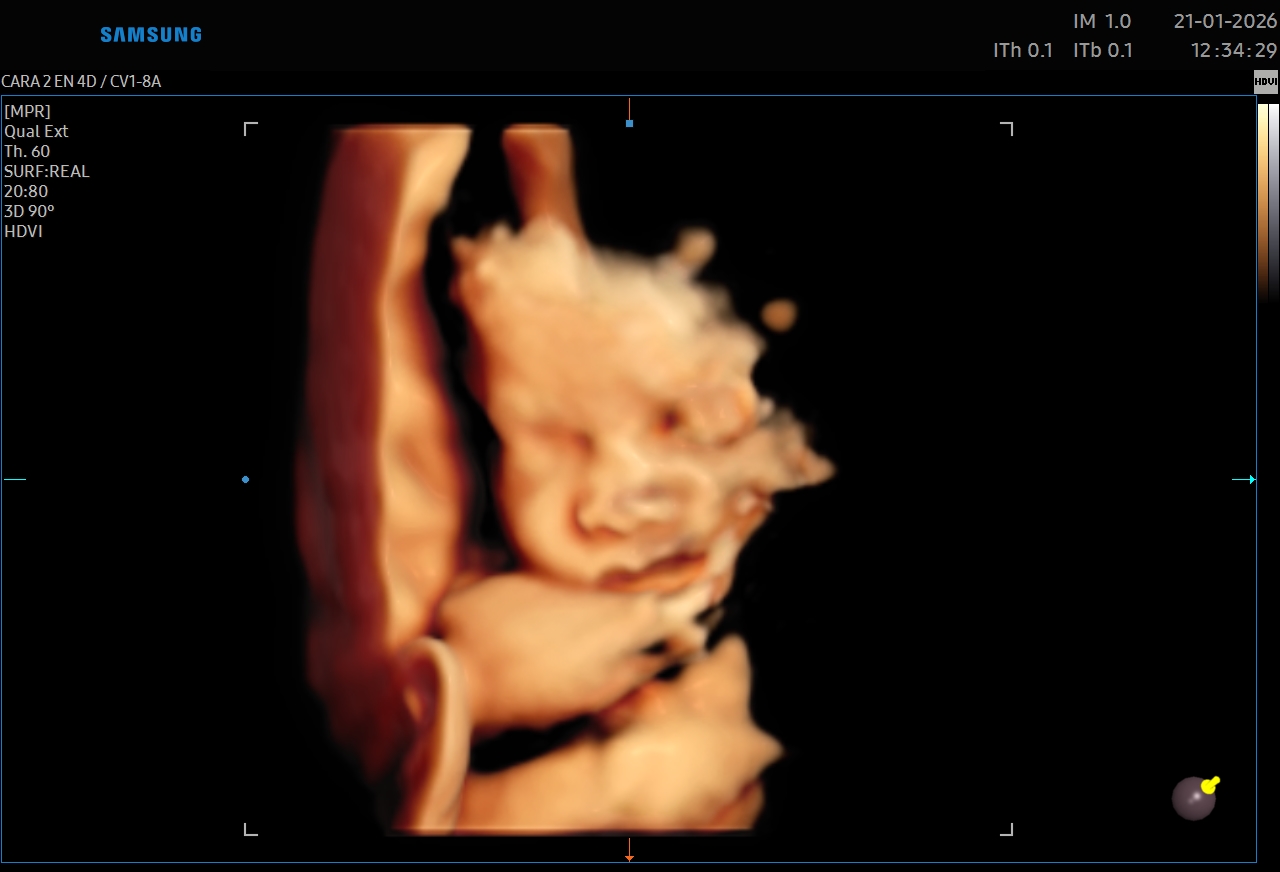

Ecografías 5D

La ecografía 5D es una experiencia única que te permite ver a tu bebé con un nivel de realismo sorprendente, capturando detalles como sus gestos, expresiones y movimientos en tiempo real.

Gracias a esta tecnología avanzada, podrás observar el rostro de tu bebé con mayor claridad, creando un vínculo emocional aún más especial antes de su nacimiento. Es el momento perfecto para compartir con tu familia y guardar recuerdos inolvidables de esta etapa tan importante.

Además de ser una experiencia hermosa, este estudio se realiza con equipos de alta tecnología y bajo supervisión médica, garantizando seguridad tanto para la mamá como para el bebé.